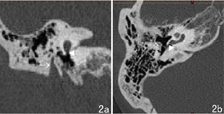

先天性外耳道闭锁病人,面神经第二膝经常前移,可前移至圆窗龛层面(图2),面神经垂直段甚至前移至颞下颌关节所在区域[7]。